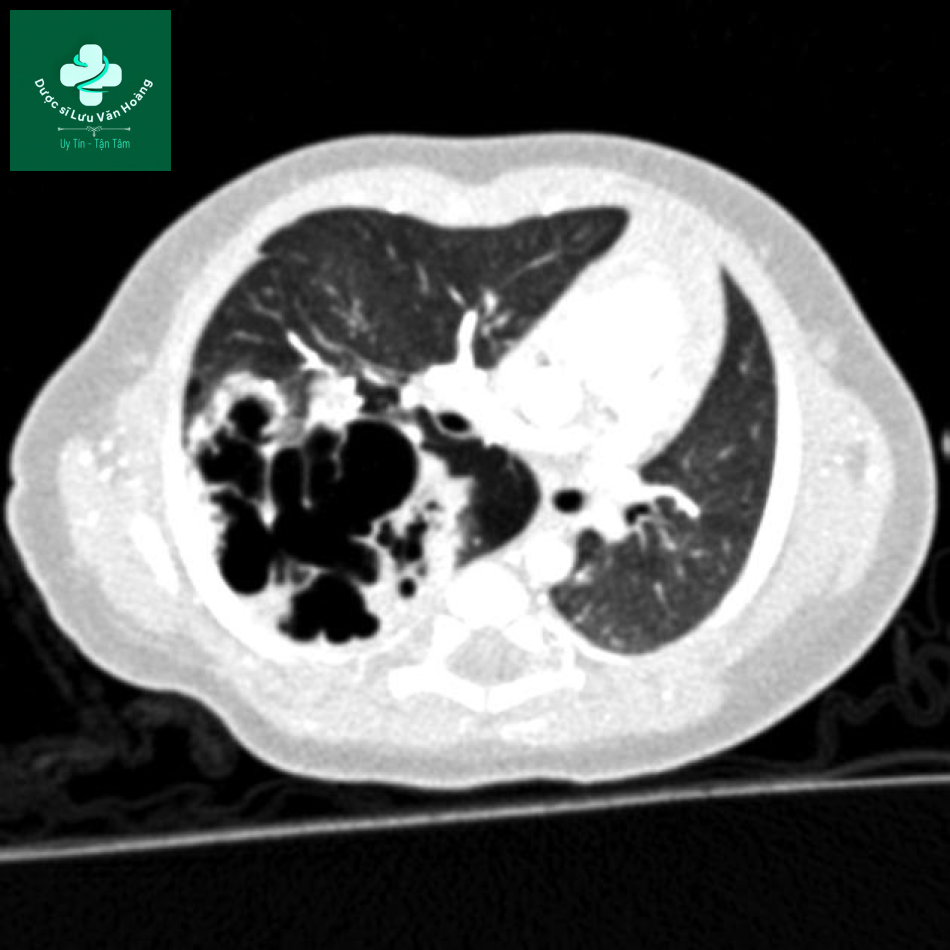

Case 3:

Trẻ nữ, 2 ngày tuổi, suy hô hấp.

Phim chụp cho thấy thùy trên phổi trái có nhiều tổn thương dạng nang lớn, gây xẹp thùy dưới và đẩy trung thất sang phải.

Chẩn đoán: CPAM type I.